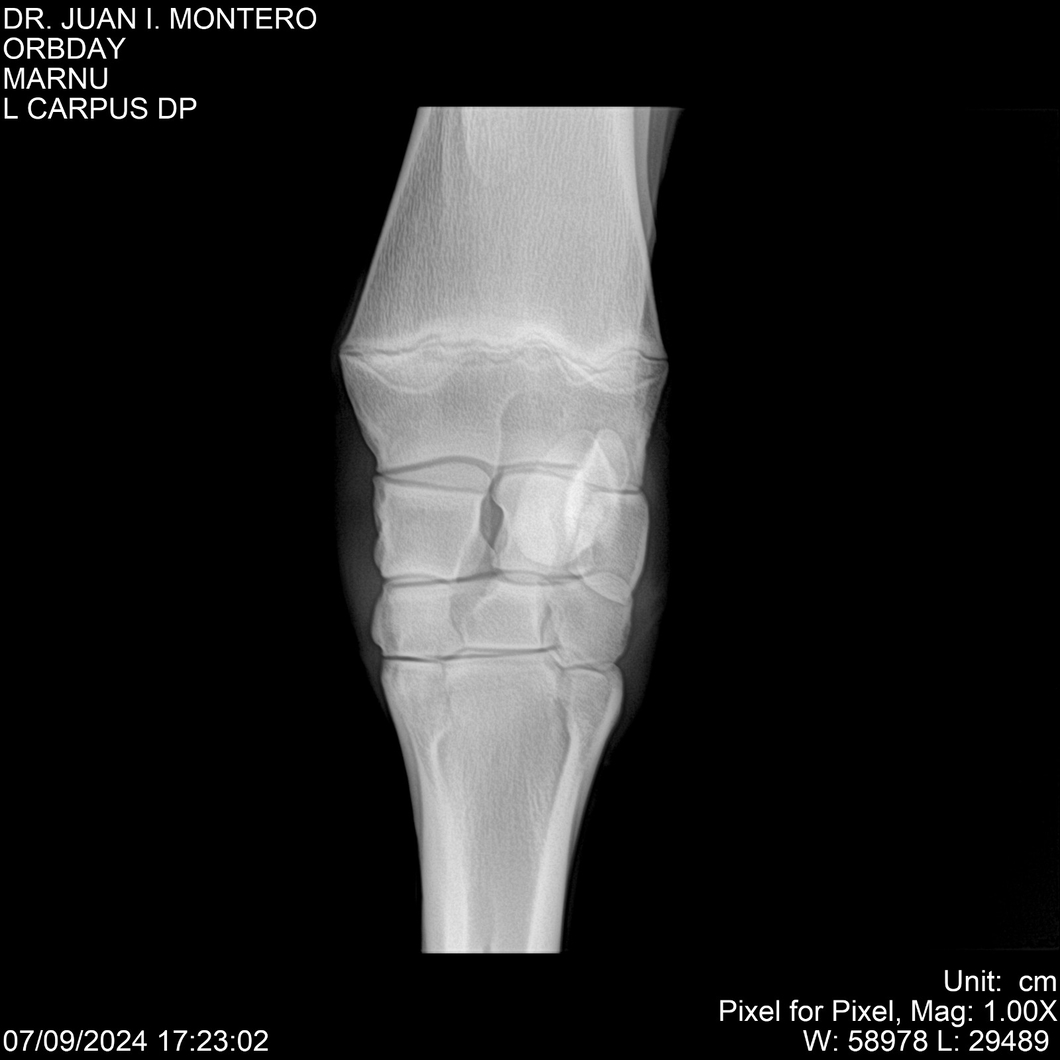

Visualizaciones